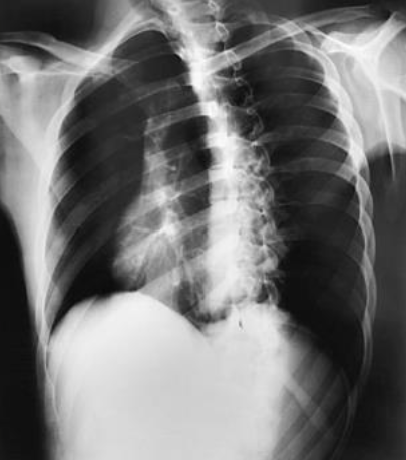

What position is demonstrated?

PA Chest